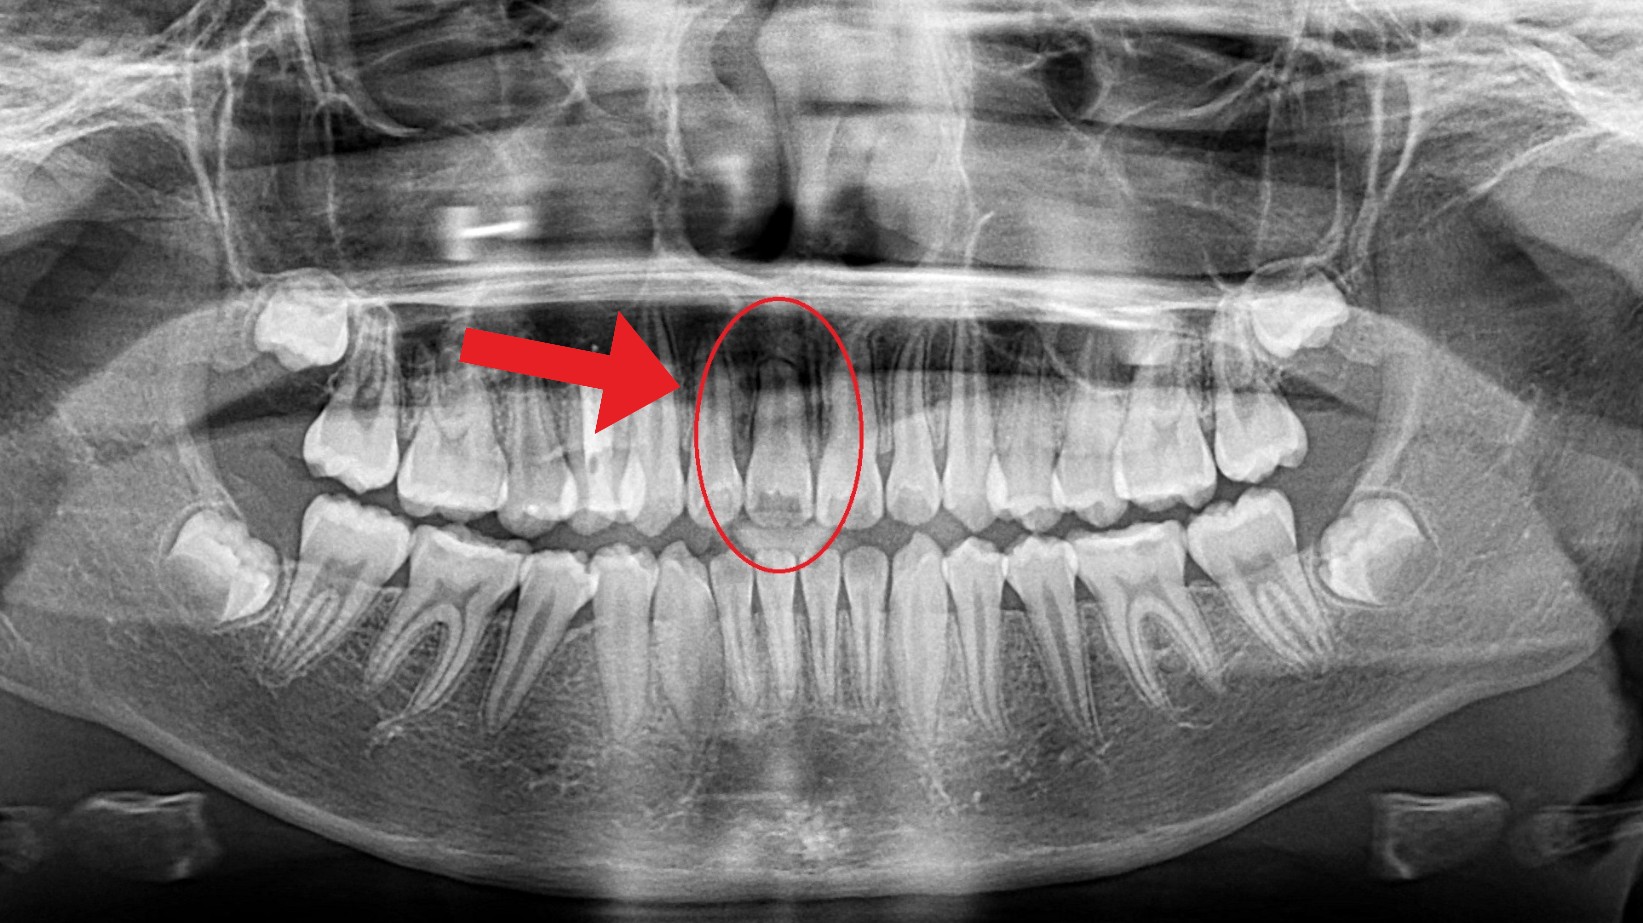

This patient came in because one of her front baby teeth had not fallen out. A panoramic X-ray showed that her permanent front tooth was impacted and stuck high in the jaw shown in the first photo.

While removal was initially recommended, we pursued a more conservative option. By attaching a small orthodontic device, we were able to gently guide the tooth into its proper position. This approach saved her natural front tooth and avoided the need for an implant—something that can never truly replace a natural smile.